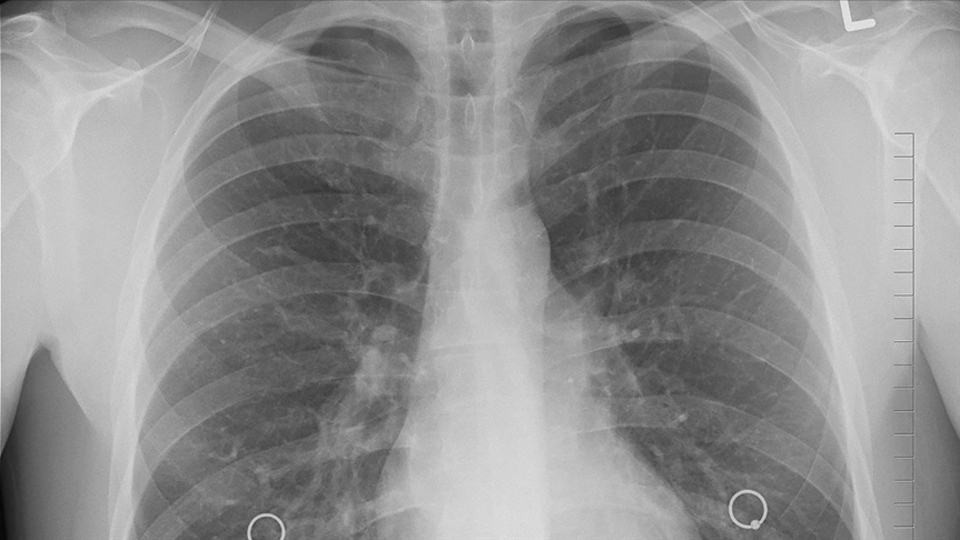

Kanser ölümlerinde ilk sırayı akciğer kanserinin aldığına işaret eden İtil, "Türkiye'de her yıl yaklaşık 35 bin insan akciğer kanseri tanısı alıyor. Ülkemiz, erkeklerde 100 bin kişide 41,7 oranı ile dünyada akciğer kanserinin en çok saptandığı ülkelerden biridir ve akciğer kanserinin en önemli nedeni halen tütün ürünleridir" ifadesini kullandı.